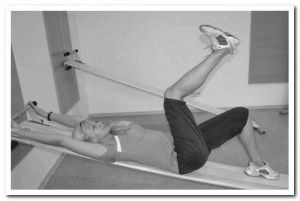

Після медикаментозної терапії, коли підуть запалення і біль, обов'язково виконання лікувальних вправ. Вони необхідні для відновлення м'язового корсету спини, підтримки його в тонусі, зміцнення хребта. Це свого роду профілактика подальшого розвитку вогнищ запалення.

Підібрати комплекс потрібно з лікуючим лікарем, орієнтуючись на тяжкість захворювання, локалізацію ураження

Не обов'язково відвідувати поліклініку для виконання гімнастики, вправи можна робити в домашніх умовах. Підібрати комплекс потрібно з лікуючим лікарем, орієнтуючись на тяжкість захворювання, локалізацію ураження. Для лікування хондроза шийного і грудного відділів хребта виконуються наступні вправи.

Наступні вправи виконуються в положенні лежачи. Лежачи на спині потрібно підтягнути ноги до живота, зігнувши їх в колінах. З такого положення потрібно торкнутися головою колін. Щоб повернутися в початкове положення, спочатку випрямляються коліна, потім шия.